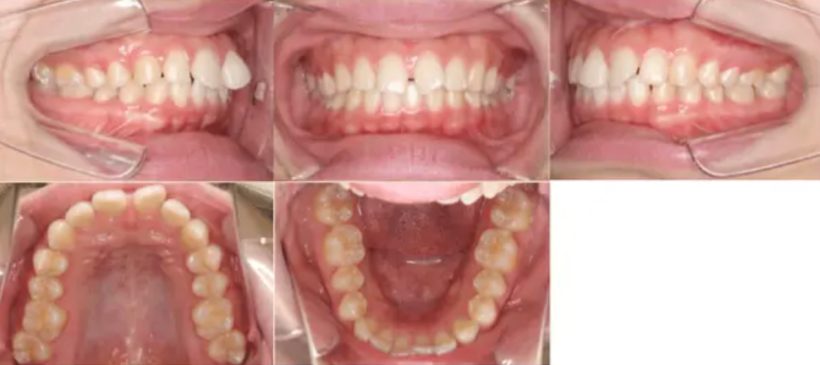

治療例②部分矯正: 23歳

| 主訴 | 前歯が出ている |

| 治療内容 | 前歯に隙間があり、ねじれてしまっていたため、マウスピース矯正で治した。 |

| 治療期間 | 6カ月 |

| 費用 | 40万円 |

【治療前】